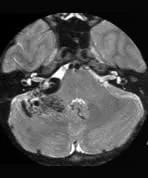

Findings

There is a large arteriovenous malformation in the right cerebello-pontine angle extending into the right fossa of Lushka. There is a large varix seen within the lesion.